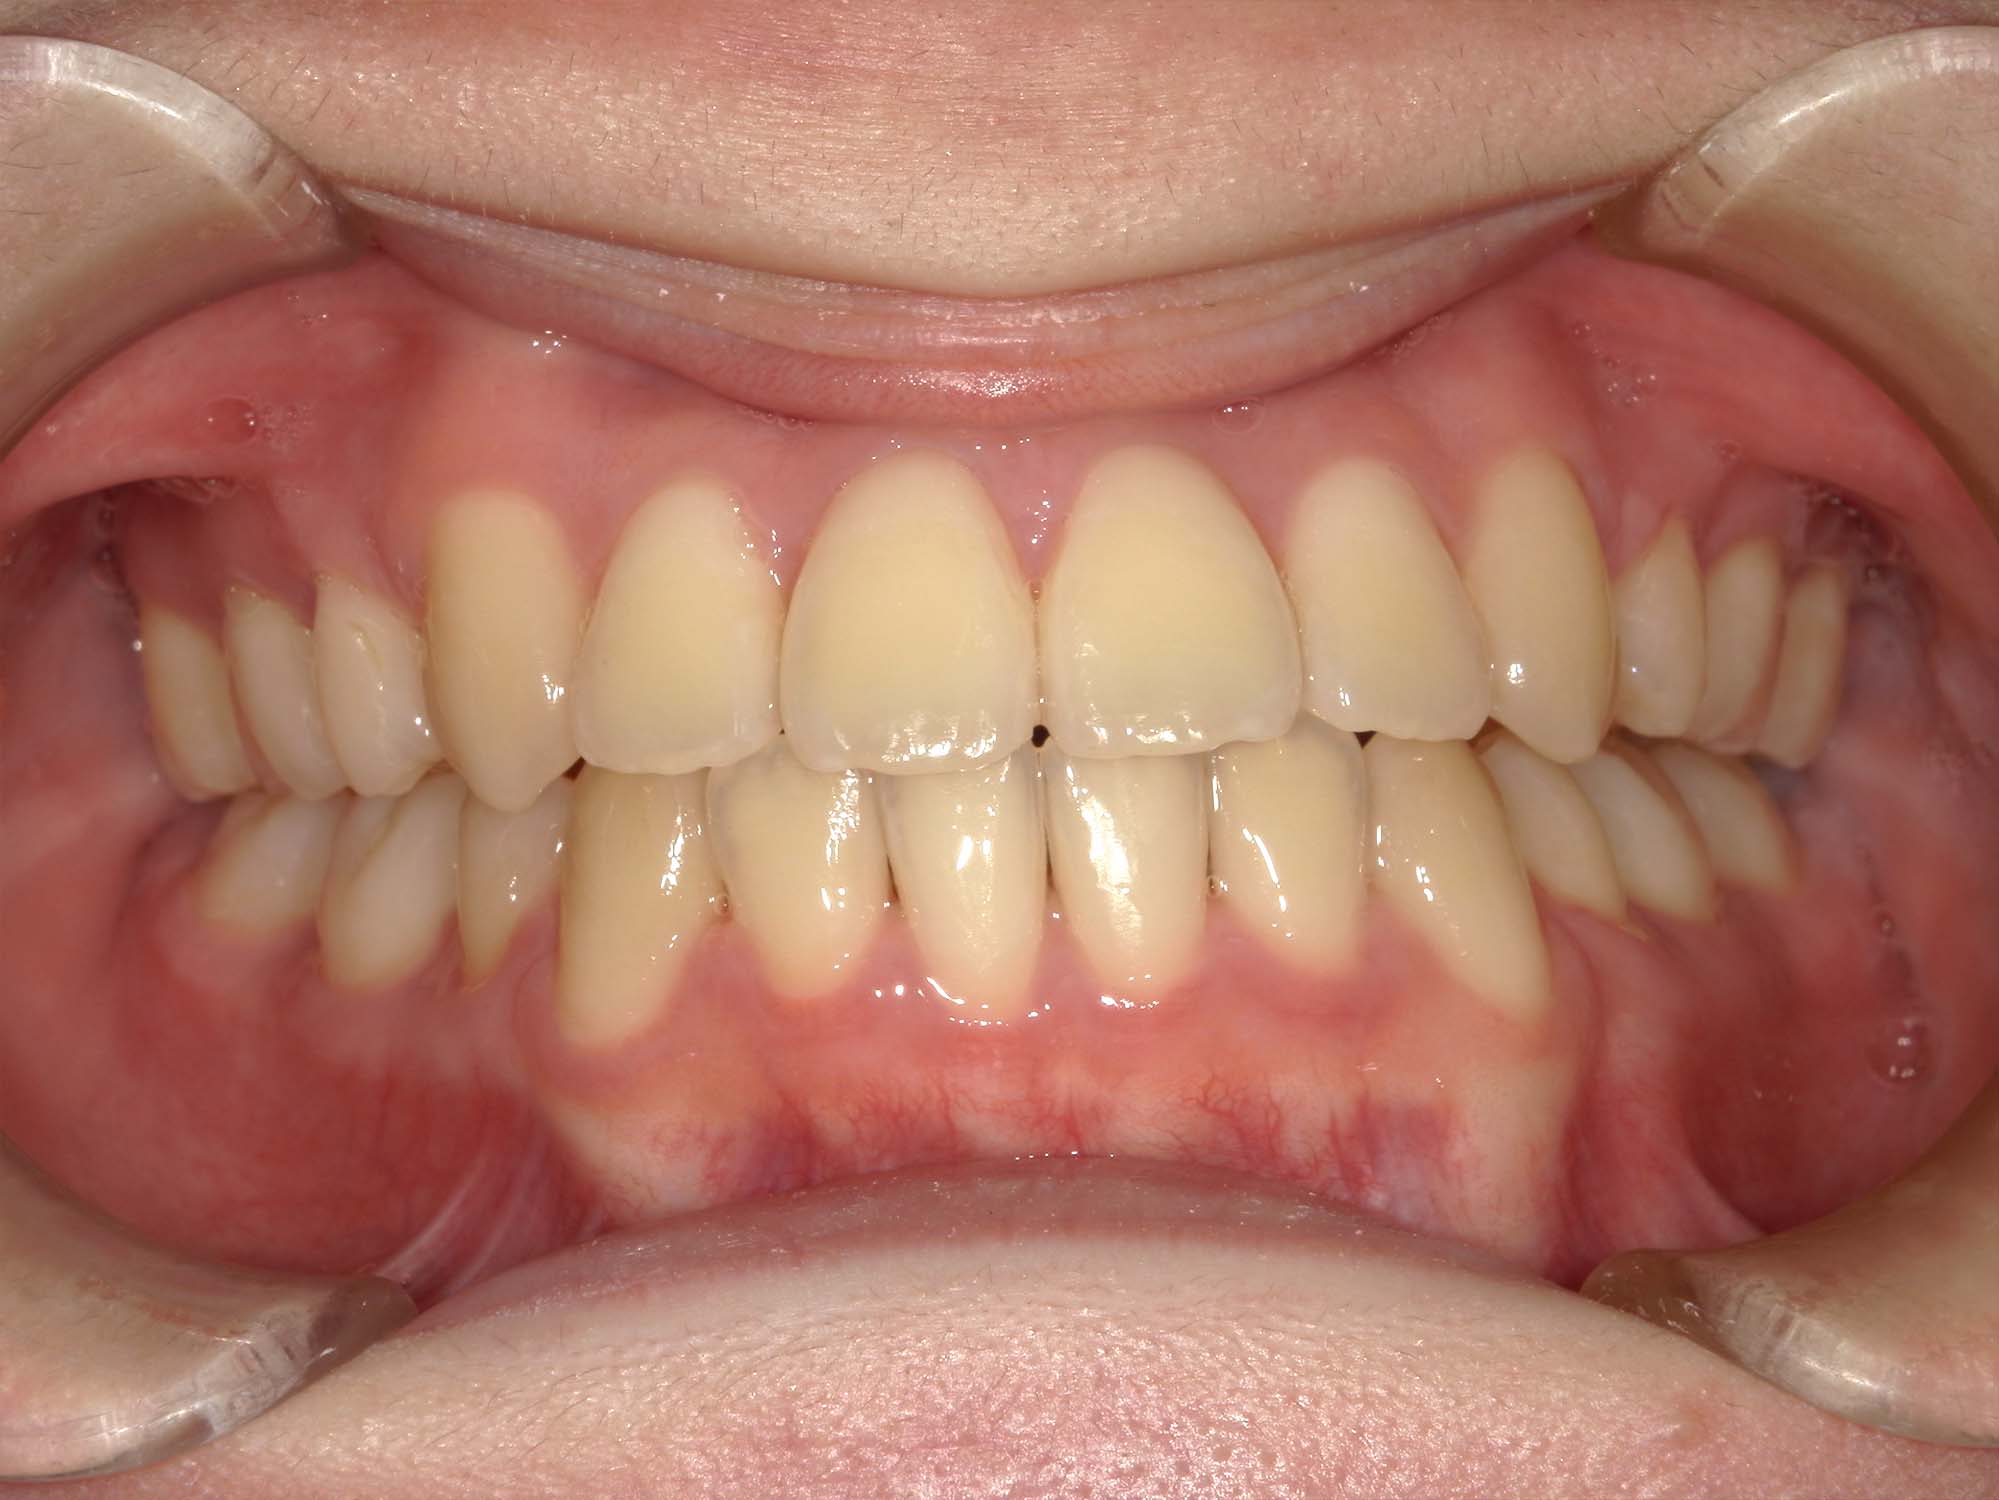

| 年齢・性別 | 15歳の女性 |

|---|---|

| 主訴 | 咬み合わせが逆であること(反対咬合)を気にされて来院された15歳7か月の女性。見た目や機能面の改善を希望されていました。 |

| 治療期間・回数 | 4年4ヶ月・28回 |

| 費用 | 900,000円 |